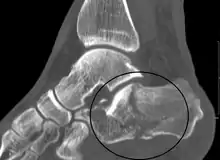

Conventional radiography is usually the initial assessment tool when a calcaneal fracture is suspected. Recommended x-ray views are (a) axial, (b) anteroposterior, (c) oblique and (d) views with dorsiflexion and internal rotation of the foot. However, conventional radiography is limited for visualization of calcaneal anatomy, especially at the subtalar joint. A CT scan is currently the imaging study of choice for evaluating calcaneal injury and has substituted conventional radiography in the classification of calcaneal fractures.[12] Axial and coronal views are obtained for proper visualization of the calcaneus, subtalar, calcaneocuboid and talonavicular joints.